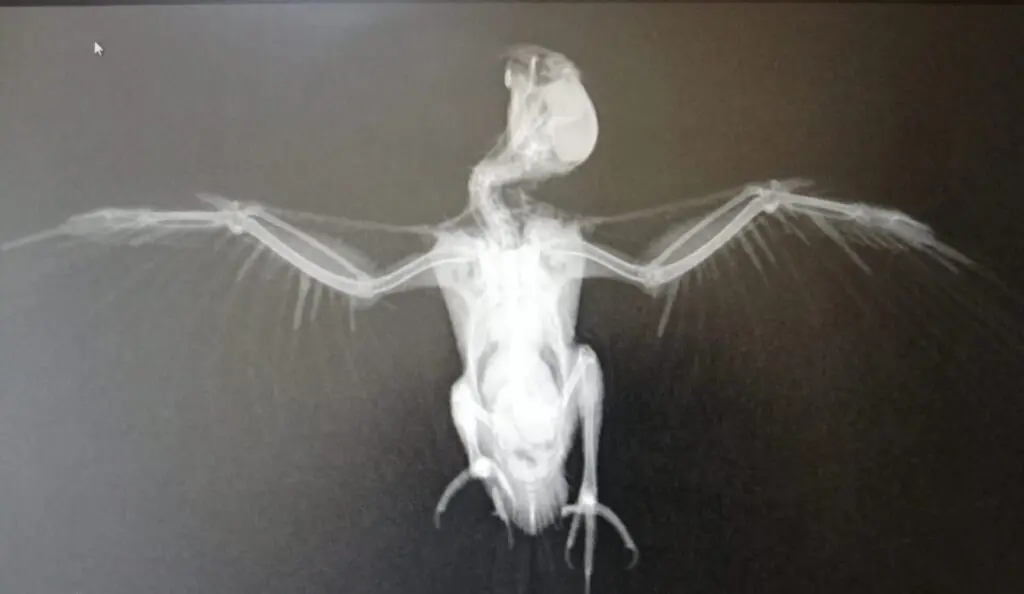

Radiología